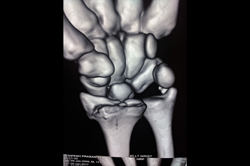

Scaphoid